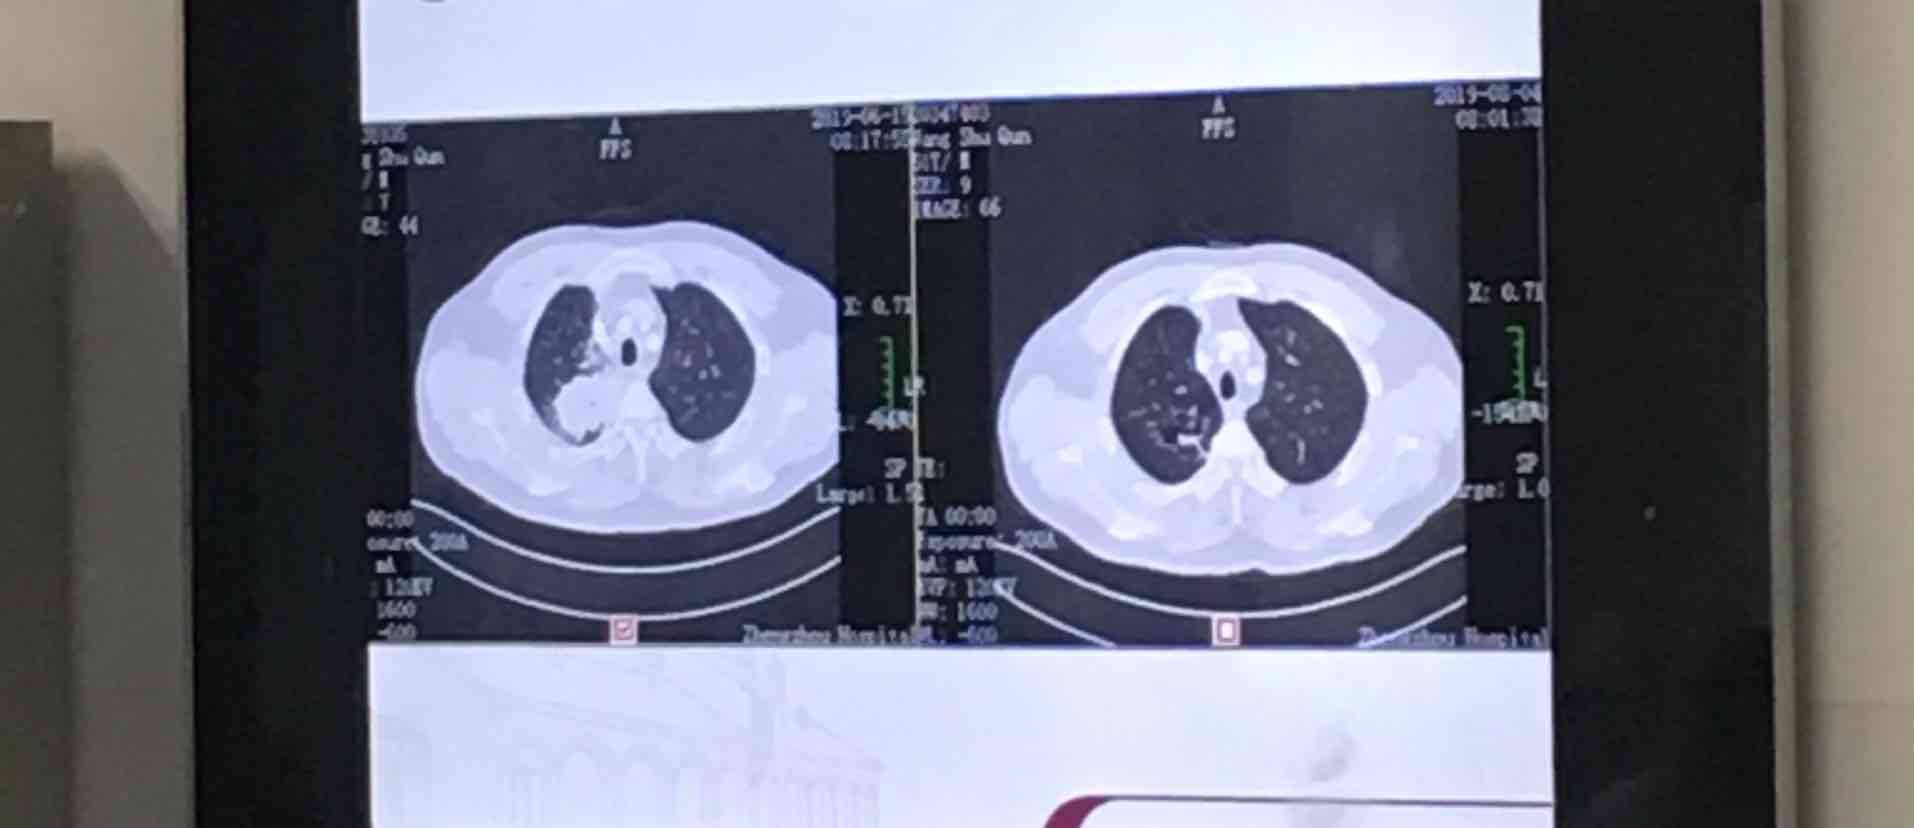

肺腺癌四期,双肺转移,纵隔及右肺门有多个小淋巴结,双颈锁骨窝多个小淋巴结糖代谢活跃,5月22号pet-ct显示最大病灶5.6^3.7,6月16号再次做ct,结果显示已经增大,6.1^3.6

此时已经超过了第三次用药的时间,被自称为我娘家人的医生告诉我,不要着急那21天一个周期的治疗,让我爸身体再恢复一周再去用药。本来应该用完药第六周做评估的,怕有肺部感染,我们就提前做了ct,结果让我大喜,最大病灶已经缩小到了2.5,但是其他小病灶没有明显缩小,只是处于稳定状态,这个地方埋个伏笔。

8月3号,我们再次来到了医院,进行全面的评估,结果再一次让我惊喜,短短的一周左右的时间,最大病灶已经不到两厘米了,其他小病灶也有明显的缩小,但并没有完全消失。我一直再问我们的主治医生,表示不相信,真的变化这么大吗,直接上图

肿瘤内科的医生都坐一起在研究我爸的疗效,哈哈。